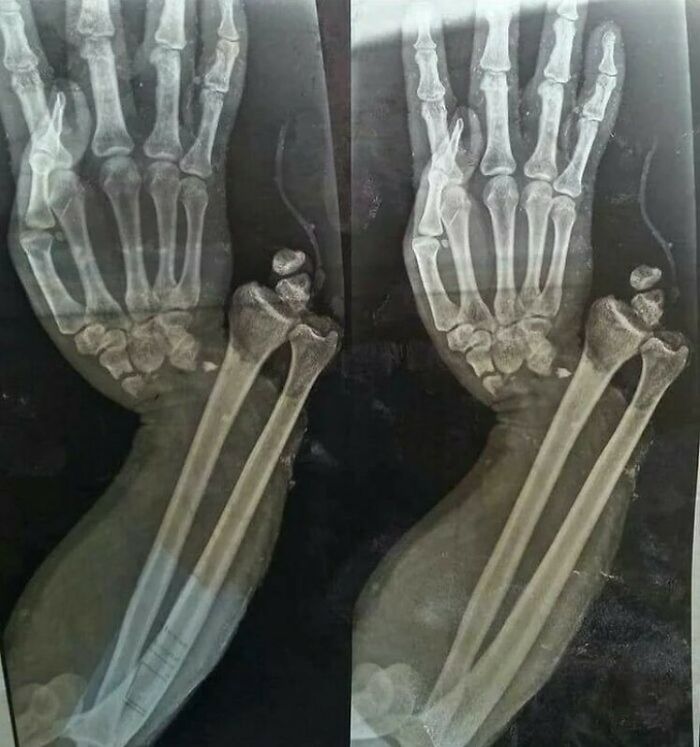

#31

Open fracture dislocation of the wrist